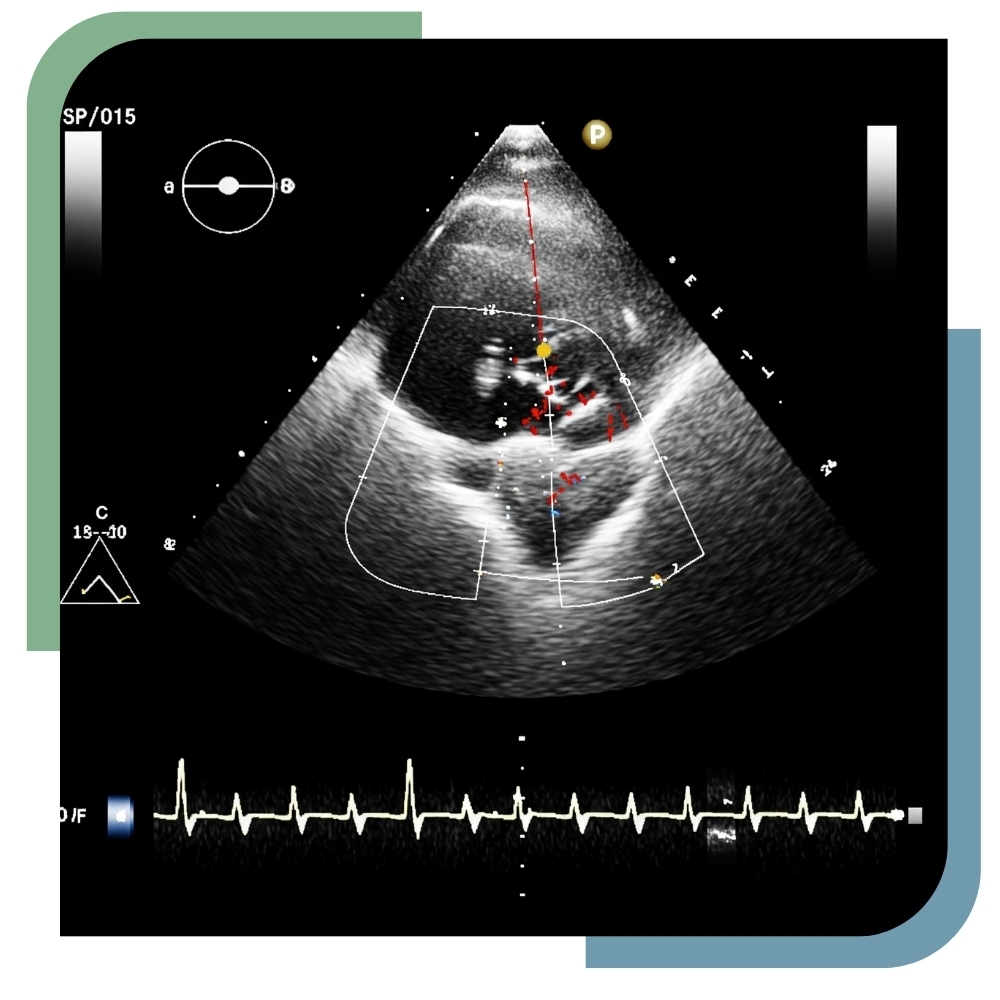

At Tirsa Healthcare, our 2D Echocardiography services offer detailed imaging of the heart’s chambers, valves, and blood flow. Performed by skilled cardiologists using high-resolution ultrasound equipment, 2D Echo helps detect structural abnormalities, heart disease, and other cardiac conditions. This non-invasive, safe procedure provides real-time insights into heart function, aiding early diagnosis and effective management. Our dedicated cardiac team ensures patient comfort, accurate reporting, and personalised care throughout the examination process.

2D Echocardiography

Evaluate heart structure and blood flow effectively.

Doppler Studies

Assess blood flow through valves and vessels.